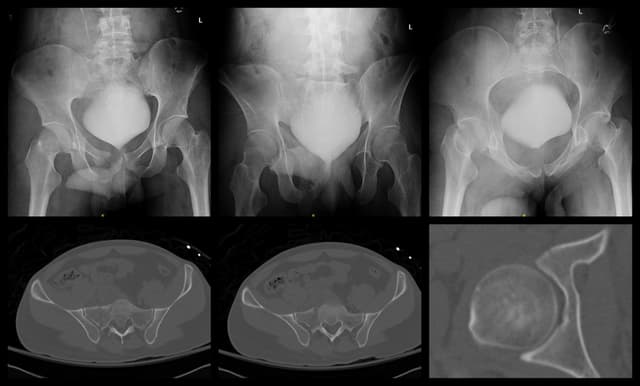

Imaging

Pre-op